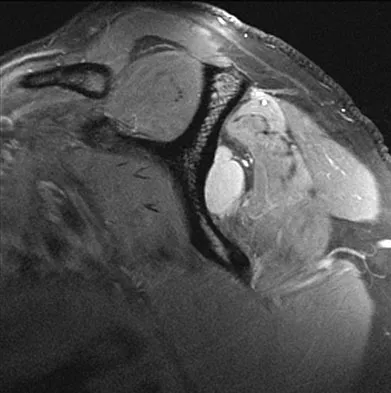

Question 53

Figure 47 shows a transverse MRI scan of a patient's left shoulder. The findings reveal which of the following abnormalities?

Explanation